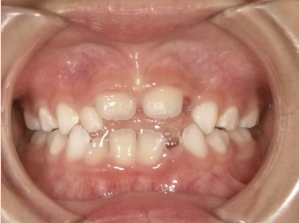

| カウンセリング・診断結果 | 前歯の生え変わり時期に来院されました。(写真①) 乳歯列期に受け口の既往があり切端咬合になりそうなため、受け口に対する矯正治療の考え方と対処法、当院のコンセプトを説明したところ治療を希望されたので診断を行いました。 診断の結果、上顎骨に対し下顎骨が長く、骨格的な構造も下顎突出型反対咬合(下顎骨が適切な位置よりも前に出ているタイプの受け口)と分かりました。 顔立ちは、中顔面が引っ込んだように見えるコンケーブに移行中です。 機能的な問題として低位舌があるため受け口の悪化が考えられることも説明し、以下の治療を提案しました。 |

| 行ったご提案・診断内容 | 成長期に行う治療と咬合治療をご提案 成長期受け口用モノブロック装置(筋機能的装置)を*MFTと併行して先行し、小学2年生以降で、拡大・前歯の調整へ移行し、咬合治療は受け口悪化予防と咬合の構築効果がある咬合治療用モノブロック装置(筋機能的咬合誘導装置)へ移行する提案をしました。 成長期治療(成長時期にお口の環境を整える治療) 咬合治療 経過観察 |